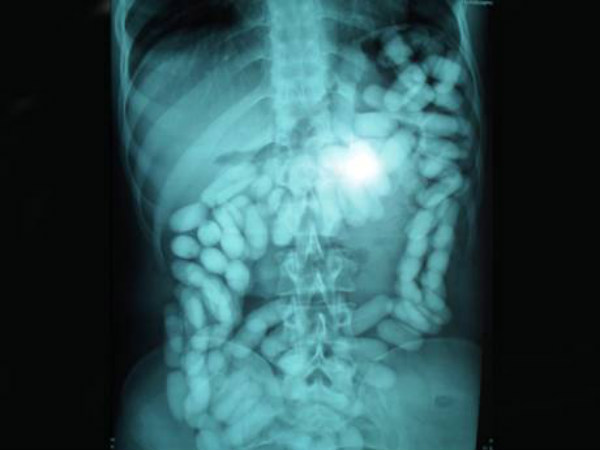

ರಷ್ಯಾದ ಚೆಲಿಯಾಬಿನ್ಸ್ಕ್ (Chelyabinsk) ಎಂಬ ಊರಿನ ಆಸ್ಪತ್ರೆಯ ಮಕ್ಕಳ ತಜ್ಞವೈದ್ಯರಾದ ಡಾ. Nikolay Rostovtsev ಎಂಬುವವರಿಗೆ 2013ರ ಪ್ರೇಮಿಗಳ ದಿನ ವಿಭಿನ್ನವಾಗಿ ಆಚರಿಸಬೇಕಾಗಿ ಬಂದಿತ್ತು. ಫೆಭ್ರವರಿಯಲ್ಲಿ ಅವರ ಬಳಿ ಹದಿನಾರು ತಿಂಗಳ ಮಗುವೊಂದನ್ನು ಕರೆದುಕೊಂಡು ಬರಲಾಗಿತ್ತು. ಈ ಮಗು ಫ್ರಿಜ್ಜಿಗೆ ಅಂಟಿಸುವ ಚಿಕ್ಕ ಚಿಕ್ಕ ಆಯಸ್ಕಾಂತಗಳನ್ನೆಲ್ಲಾ ಒಂದೊಂದಾಗಿ ನುಂಗಿತ್ತು. ಎಕ್ಸ್ ರೇ ಯಲ್ಲಿ ಇದು ಸ್ಪಷ್ಟವಾಗಿ ಕಂಡ ಬಳಿಕ ಅನಿವಾರ್ಯವಾಗಿ ವೈದ್ಯರು ಶಸ್ತ್ರಕ್ರಿಯೆ ನಡೆಸಿ ಒಟ್ಟು ನಲವತ್ತೆರಡು ಚಿಕ್ಕಚಿಕ್ಕ ಆಯಸ್ಕಾಂಗಳನ್ನು ಹೊರತೆಗೆದರು. ಮುಂದಿನ ಸ್ಲೈಡ್ ಕ್ಲಿಕ್ ಮಾಡಿ

ಆಯಸ್ಕಾಂತ

ಮಗುವನ್ನು ಅಡುಗೆ ಮನೆಯಲ್ಲಿ ಆಟವಾಡಲು ಬಿಟ್ಟು ತನ್ನ ಕೆಲಸಕ್ಕೆ ಹೋದ ತಾಯಿ ಹಿಂದಿರುಗಿ ಬಂದಾಗ ಅಲ್ಲಿದ್ದಾ ಚಿಕ್ಕ ಆಯಸ್ಕಾಂತಗಳೆಲ್ಲಾ ಕಾಣೆಯಾಗಿದ್ದು ದುಗುಡಕ್ಕೆ ಕಾರಣವಾಗಿತ್ತು. ತಕ್ಷಣ ಸಮೀಪದ ಆಸ್ಪತ್ರೆಗೆ ಕರೆದುಕೊಂಡು ಹೋಗಿ ಎಕ್ಸ್ ರೇ ತೆಗೆಸಿ ಆಯಸ್ಕಾಂತಗಳು ಇರುವುದು ಕಂಡುಬಂದ ಬಳಿಕ ದೊಡ್ಡಾಸ್ಪತ್ರೆಗೆ ಕರೆದೊಯ್ಯಲಾಗಿತ್ತು.